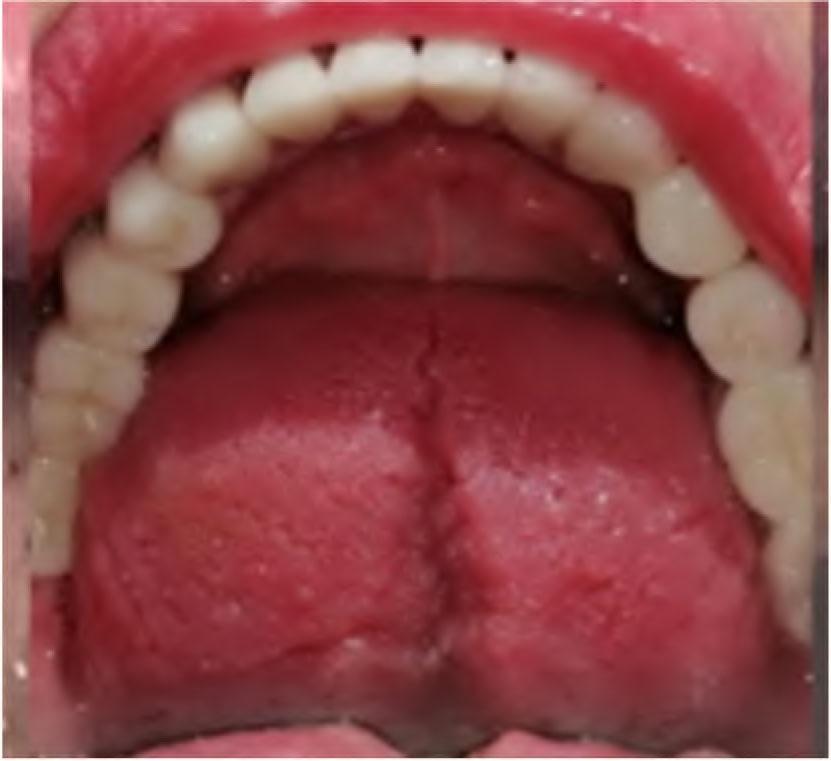

Intraoral and radiograph examination verified that 26 and 46 were missing and the endodontic treatment of 16 was no adequately performed. Caries lesions were found on the mesial surfaces of 11, 21 and 12. There was no pocket depth of over 2 mm or mobility around any of the remaining teeth. Panoramic radiograph confirmed that all the maxillary and mandibular teeth had favorable crown/root ratio of 2:3 (Figure 2). The patient’s oral hygiene was good.

Panoramic radiograph before treatment